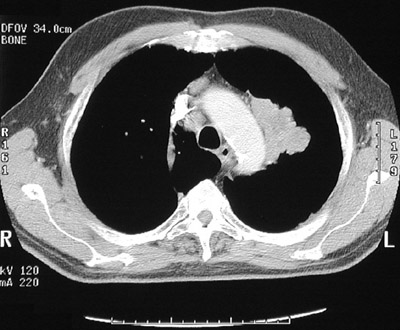

| This chest CT scan in "bone window" highlights a large, solitary hilar mass that proved to be a squamous cell carcinoma of the left upper lobe of lung. Since squamous cell carcinomas are often endobronchial in origin, they can exfoliate cells that can be found in sputum samples for cytologic analysis. They can be seen and biopsied on bronchoscopy. Unfortunately, these are often late findings. |